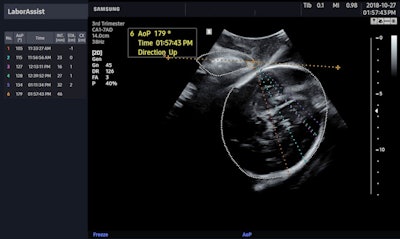

BiometryAssist provides physicians with fetal measurements in about 85 milliseconds, according to Samsung. Meanwhile, LaborAssist provides estimates of fetal AoP and head direction, which physicians can use to monitor real-time progression of delivery and determine the best delivery method, Samsung noted.

Samsung also announced that it will continue its partnership with Intel for its other artificial intelligence ultrasound solutions, including Nerve Tracking, SW Beamforming, and AI Module.